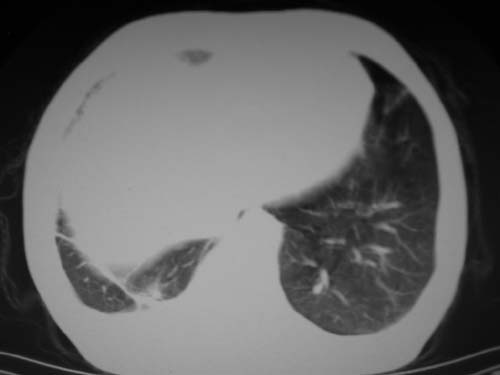

男,80岁

左下肺静脉扩张,原因?建议cta

左肺动脉异常增粗,建议增强。

1)考虑肺动脉狭窄。2)右肺上叶继发性肺结核。3)右侧胸膜增厚、钙化,左侧胸膜反应。

肺动脉瘤。建议先行ct增强扫描

左肺动脉异常增粗,考虑肺动脉狭窄可能。

左肺动脉异常增粗,建议ct增强,排除肺门肿瘤

1)考虑左肺动脉瘤可能性大,建议增强。2)右肺上叶继发性肺结核。3)右侧胸膜增厚、钙化,左侧胸膜反应。

肺动脉段突出,左右肺门不等大,左肺门明显增大,肺动脉干及左肺动脉明显增宽,考虑先天性肺动脉狭窄瓣膜狭窄型。

)考虑肺动脉扩张,右心室增大,主动脉弓段正常位弓后段明显变小(不会是动脉导客未闭吧,不知患者有何症状病史)0。2)右肺上叶继发性肺结核。3)右侧胸膜增厚、钙化,左侧胸膜反应。

结合患者年龄,不除外左下肺扩张性动脉瘤,建议胸透是否有扩张性博动,以便确诊。

肺动脉高压,左肺动脉瘤样扩张。